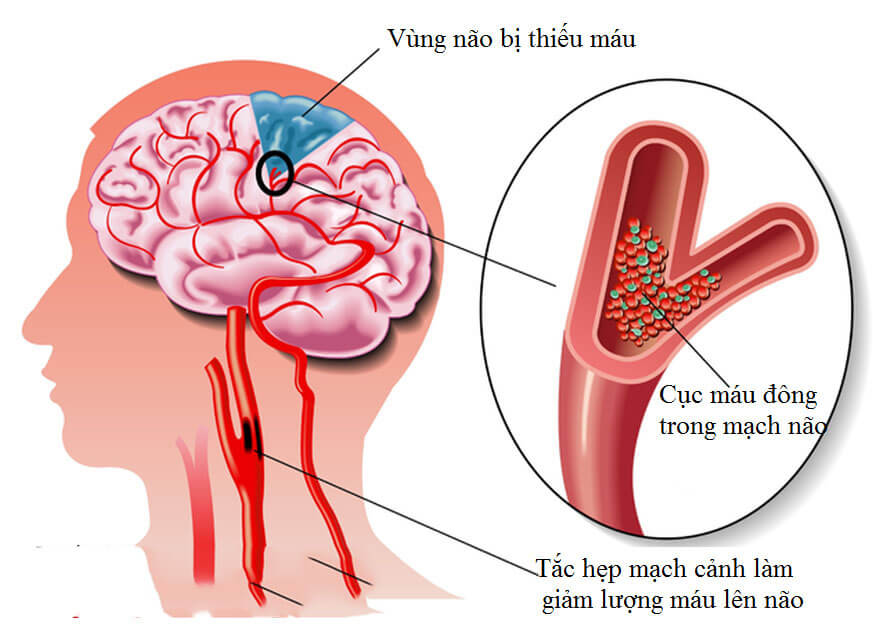

- Tai biến mạch máu não: Khi các buồng trên của tim bị tăng áp lực, cục máu đông có thể hình thành do lưu lượng máu giảm. Cục máu đông này sau đó có thể đi từ tim đến não, nơi nó có thể đi vào một mạch máu nhỏ hơn và gây ra đột quỵ.

Khi các buồng trên của tim bị tăng áp lực, cục máu đông có thể hình thành do lưu lượng máu giảm. Cục máu đông này sau đó có thể đi từ tim đến não, nơi nó có thể đi vào một mạch máu nhỏ hơn và gây ra đột quỵ.

Khi các buồng trên của tim bị tăng áp lực, cục máu đông có thể hình thành do lưu lượng máu giảm. Cục máu đông này sau đó có thể đi từ tim đến não, nơi nó có thể đi vào một mạch máu nhỏ hơn và gây ra đột quỵ.